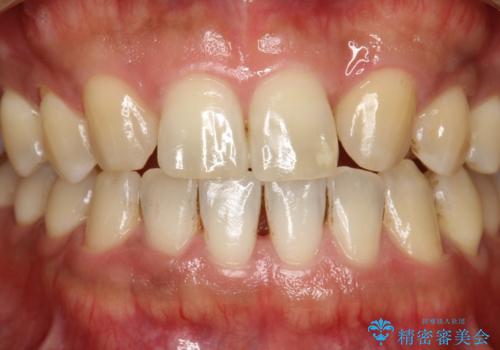

- 全体的な着色(ステイン)、黄ばみが気になるとのことで、来院されました。着色(ステイン)などの付着量が多かったためPMTCの60分コースを行いました。

PMTCを行うと、着色(ステイン)や歯石などを除去することができます。

PMTCは、歯科医院にて専門的な機械・材料を使用して行う専用クリーニングです。着色(ステイン)や歯石を取り除くことで、ご自身の本来の歯の色となります。また、施術後にはスッキリとした爽快感あ得られたり、歯の舌ざわりがツルツルになり気持ちがいいです。